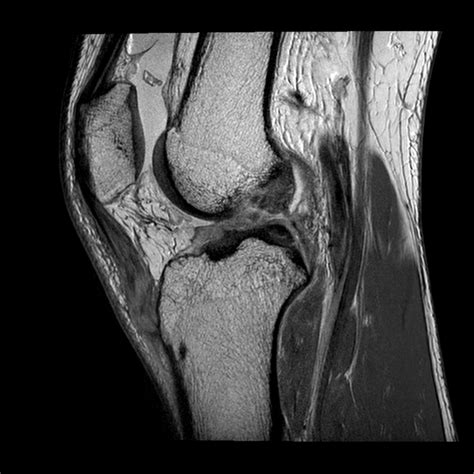

Avulsion fracture (small) of the lateral surface of the lateral tibial condyle. A segond fracture is an avulsion fracture located in the lateral aspect of the tibial plateau of the segond fracture:

A small avulsion that reflects major ligamentous damage. Imaging findings and clinical significance. Reverse segond fracture, as its name suggests.

Imaging findings and clinical significance. Nlm pubmed google websites google images quackwatch drugstore.com. Segond fracture is an avulsion fracture of the knee that involves the lateral aspect of the tibial plateau and is very frequently (~75% of cases) associated with disruption of the anterior cruciate ligament. Reverse segond fracture, as its name suggests. Segond fracture associated with increased probability of other soft tissue such as acl rupture; Search other sites for 'segond fracture'. All will feature in our upcoming emergency radiology course. Introduction the reverse segond fracture was rst reported by hall. A segond fracture is an avulsion of the lateral capsular ligament. Avulsion fracture (small) of the lateral surface of the lateral tibial condyle. The segond fracture of the proximal tibia: Segond fracture is typically the result of abnormal varus, or bowing, stress to the knee, combined with internal rotation of the tibia. It is frequently a varus stress that leads to a lateral collateral complex injury. The segond fracture is a type of avulsion fracture (soft tissue structures tearing off bits of their combined acl reconstruction and segond fracture fixation fails to abolish anterolateral rotatory. Segond fracture = avulsion of the anterolateral aspect of the lateral tibial plateau. Paul ferdinand segond was a french surgeon who not only was a knee specialist but also perfected the vaginal hysterectomy. ✪ fractures associated with acl injury: